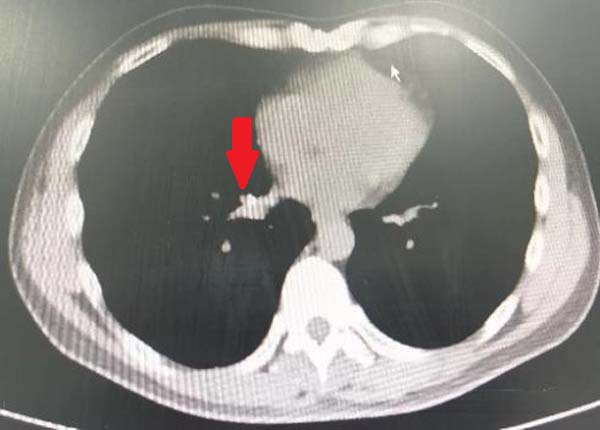

图1.胸部CT显示右肺下叶内基底段支气管结石影

周云芝带领团队反复阅读片子,认真分析结石位置与周围血管的关系,设计了取石方案,制定术中风险预案,同时在术前对陈先生进行了耐心的病情沟通及详细的手术讲解,给予了陈先生莫大的勇气及信心。